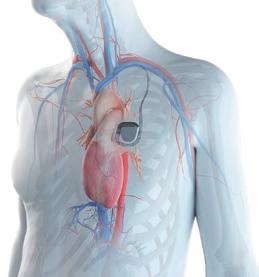

Novi iskorak u pružanju zdravstvenih usluga Ova, 2024. godina ostaće upamćena u istoriji Banje Vrućice kao godina u kojoj je napravljen veliki iskorak u pružanju zdravstvenih usluga. U novom objektu „Hercegovina-blok B“ koji će biti otvoren do kraja ove, 2024. godine, nalazi se veliki dijagnostički centar sa magnetnom rezonancom, CT-om i dve operacione sale te ambulante u kojima će se vršiti brojni specijalistički pregledi. To je najveća investicija u poslednjih pet godina. Dijagnostički centar opremljen je najmodernijom tehnologijom koja omogućava brzu i preciznu dijagnostiku različitih zdravstvenih stanja. Centar nudi širok spektar usluga, uključujući magnetnu rezonancu, CT skener, ultrazvučne i endoskopske preglede. Siemensova MRI od 1,5T pruža visokokvalitetne slike koje omogućavaju detaljnu analizu mekih tkiva, kostiju i drugih struktura unutar tela. Pored toga, CT aparat Siemens Somatom Go Top 64 Slice omogućava brze i precizne preglede, pružajući dvodimenzionalne i trodimenzionalne slike koje su ključne za pravilnu dijagnostiku. Tu su i angioskopije za vizuelizaciju krvnih sudova, što pomaže u dijagnostici cirkulatornih stanja. Na usluzi su takođe i kardiološ-

ke neinvazivne dijagnostičke procedure, kao ergometrija, ultrazvuk srca, EKG i Holter monitoring (krvnog pritiska i srčanog ritma), koje omogućavaju detaljno praćenje i analizu stanja srca pacijenata. Dijagnostički centar pruža pravovremenu dijagnostiku i pravilan plan lečenja. Operacioni blok je opremljen najsavremenijom medicinskom opremom gde se obavljaju procedure

Banja Vrućica prednjači u zdravstvenom turizmu, primenjujući holistički pristup zdravlju, sa širokim spektrom preventivnih, zdravstvenih, kao i usluga rehabilitacije, a naročito rehabilitacije kardiovaskularnih bolesnika. Inače, veoma su retke banje koje se bave rehabilitacijom ovih bolesnika, s obzirom na to da je to najrizičnija grupa i njihova rehabilitacija traži specifične uslove. Termomineralna voda u srcu prirode u kojoj se Banja ugnezdila, specifičnih je karakteristika i jedna je od retkih koja dozvoljava srčanim bolesnicima da je koriste. Voda Banje Vrućice pripada kategoriji kalcijum-natrijum-hidrokarbonatnim-hloridnim-ugljenokiselim-fluoridnim, mineralnim, hipertermalnim vodama. Mineralno vrelo sadrži visoku koncentraciju negativnih jona, koji uzrokuju osećaj fizičkog i psihičkog blagostanja. Ona se može koristiti za banjanje u kadama za hidroterapiju u bazenu, ali se može i piti, inhalirati ili nanositi na kožu kao oblog. Sva lekovitost prirode sada je spojena sa svim što savremena medicina nudi. Stručno medicinsko osoblje, usavršen način rada i najmodernija oprema, podigli su zdravstvenu uslugu Banje Vrućice na višu lestvicu,

Medicinska rehabilitacija, pre svega, podrazumeva kardiovaskularnu rehabilitaciju, jer se još od 1959. Banja Vrućica bavi lečenjem i rehabilitacijom kardiovaskularnih pacijenata. Rehabilitacija se provodi u salama opremljenim za jutarnje vežbe, za intervalni trening, a između toga i trening šetnje po uređenim stazama, a sve uz nadzor visokoobučenih terapeuta za rad sa kardiološkim pacijentima. Tajna uspešnog lečenja i rehabilitacije srčanih bolesnika u Banji Vrućici je u lekovitoj termomineralnoj vodi, jedinstvenoj u ovom delu Evrope. Ona je zbog svog sastava i temperature prava blagodet, jer rasterećuje srce kao pumpu, što, opet, omogućava poboljšanje cirkulacije u krvotoku. Time se obezbeđuje rehabilitacija srca, odnosno celog krvotoka! Tu je i Fizijatrijsko-reumatološka re-